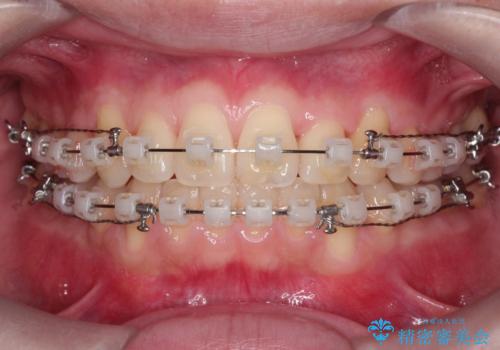

【クリア装置】前歯の凸凹を綺麗にしたい

- 前歯の凸凹を主訴に来院されました。

マウスピース矯正も適応でしたが、ワイヤー矯正を希望され治療を行なっております

治療期間も短く大変満足していただきました。